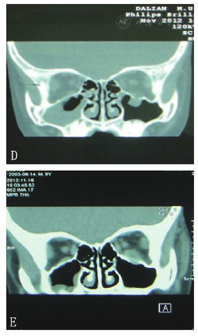

23例患者手术前后视力差异无统计学意义(P> 0.05),术前21例复视,20例眼球运动受限,2例眼球内陷,术前CT显示眶壁骨折及软组织嵌顿;术后6个月,患者眼球凹陷均矫正,2例患者残留复视、眼球上转受限,其余患者均矫正,CT显示组织解剖复位。

23例患者手术前后视力无统计学差异。术前21例次患者诉复视,20例次患者眼球运动受限、转动痛,2例次患者眼球凹陷,16例次患者有不同程度的恶心、呕吐,被动牵拉试验均阳性,23例次患者眼眶CT均明确显示骨折存在及软组织箍闭。术后6个月,患者眼球凹陷均矫正,2例患者残留复视、眼球上转受限,其余患者复视及眼球运动受限均矫正,CT均显示骨折对位、对线修复良好,组织完全解剖复位。23例患者术后无继发性睑内翻、下睑退缩、眶下神经麻痹发生,无1例患者发生內植物排斥反应及感染(图1)。

儿童Trapdoor眼眶骨折与成人爆裂性眼眶骨折在骨折类型、临床表现、手术时机、手术修复方式存在很大差异。儿童的眼眶、鼻窦解剖结构、骨生理条件特殊,儿童眼眶眶壁由未成熟骨构成,这类骨含有更多的骨细胞、成骨细胞,钙化骨组织少,该未成熟骨柔韧性、弹性更好,受创伤时不易折断;并且毗邻儿童眼眶的上颌窦发育不完全,含气量少,对眼眶下壁有一定程度的支撑作用,因此当儿童眶周受到钝性撞击引起的眼眶骨折多为线性、骨缺损较小、活瓣门样的"青枝样骨折"[5],CT多表现为"水滴样"组织嵌顿(图2)。本研究中19/23 (82.6%)例患者术前CT表现"水滴样"骨折,考虑为软组织嵌顿于骨折线引起。由于眶壁缺损较小,伤后早期组织水肿,儿童Trapdoor眼眶骨折患者少有眼球凹陷,本研究病例中仅有2例患儿术前有眼球凹陷,而成年人爆裂性眼眶骨折多数存在眼球凹陷。本研究中16/23 (59.5%)例的患儿出现恶心呕吐等胃肠道反应是由于眶内组织从骨折缝隙内疝出,导致眶内组织箍闭后兴奋迷走神经,故患者反射性表现为恶性、呕吐、甚至心律失常。儿童Trapdoor眼眶骨折特征表现为复视、眼球运动受限,本研究中20/23 (89.5%)例存在复视及眼球运动受限。由于眶内组织嵌顿,患者同时可表现为眼球转动痛及被动牵拉试验阳性。对于儿童Trapdoor眼眶骨折患者,被动牵拉试验不仅是检查,也是一种治疗手段,对于部分骨折患者眶内组织嵌顿较轻,牵拉眼球可将箍闭的组织从骨折缝中拉出,解除眼外肌等眶内组织的嵌顿,恢复血供。对于手术指征的选择,如果眶部CT证实Trapdoor骨折,同时有眼外肌箍闭于骨折处,并且被动牵拉试验无效,应早期手术治疗。成年人爆裂性眼眶骨折患者眼球运动受限并非软组织嵌顿于骨折处导致,通常与创伤造成组织出血、水肿、神经损伤有关,待出血、水肿吸收后,部分患者眼球运动受限可好转,同时患者眼球凹陷基本稳定,可择期行手术治疗[6]。对于儿童Trapdoor眼眶骨折,由于眶内组织嵌顿于骨折缝隙,如果处理不及时会因眼外肌缺血导致眼外肌坏死、纤维化,术后因眼外肌功能差,患者可表现为持续性复视,眼球运动受限甚至斜视及眼球固定[7]。本研究中21/23 (91.3%)例患者术后规律眼肌训练,术后6个月复视及眼肌运动受限均矫正,2例患者残留眼球转动受限及复视,考虑与48 h后接受手术治疗有关。因此,对儿童Trapdoor眼眶骨折患者应早期手术治疗,解除眼外肌的嵌顿,恢复其血供,目前认为48 h内手术最佳,越早手术患者术后恢复效果越好[8]。